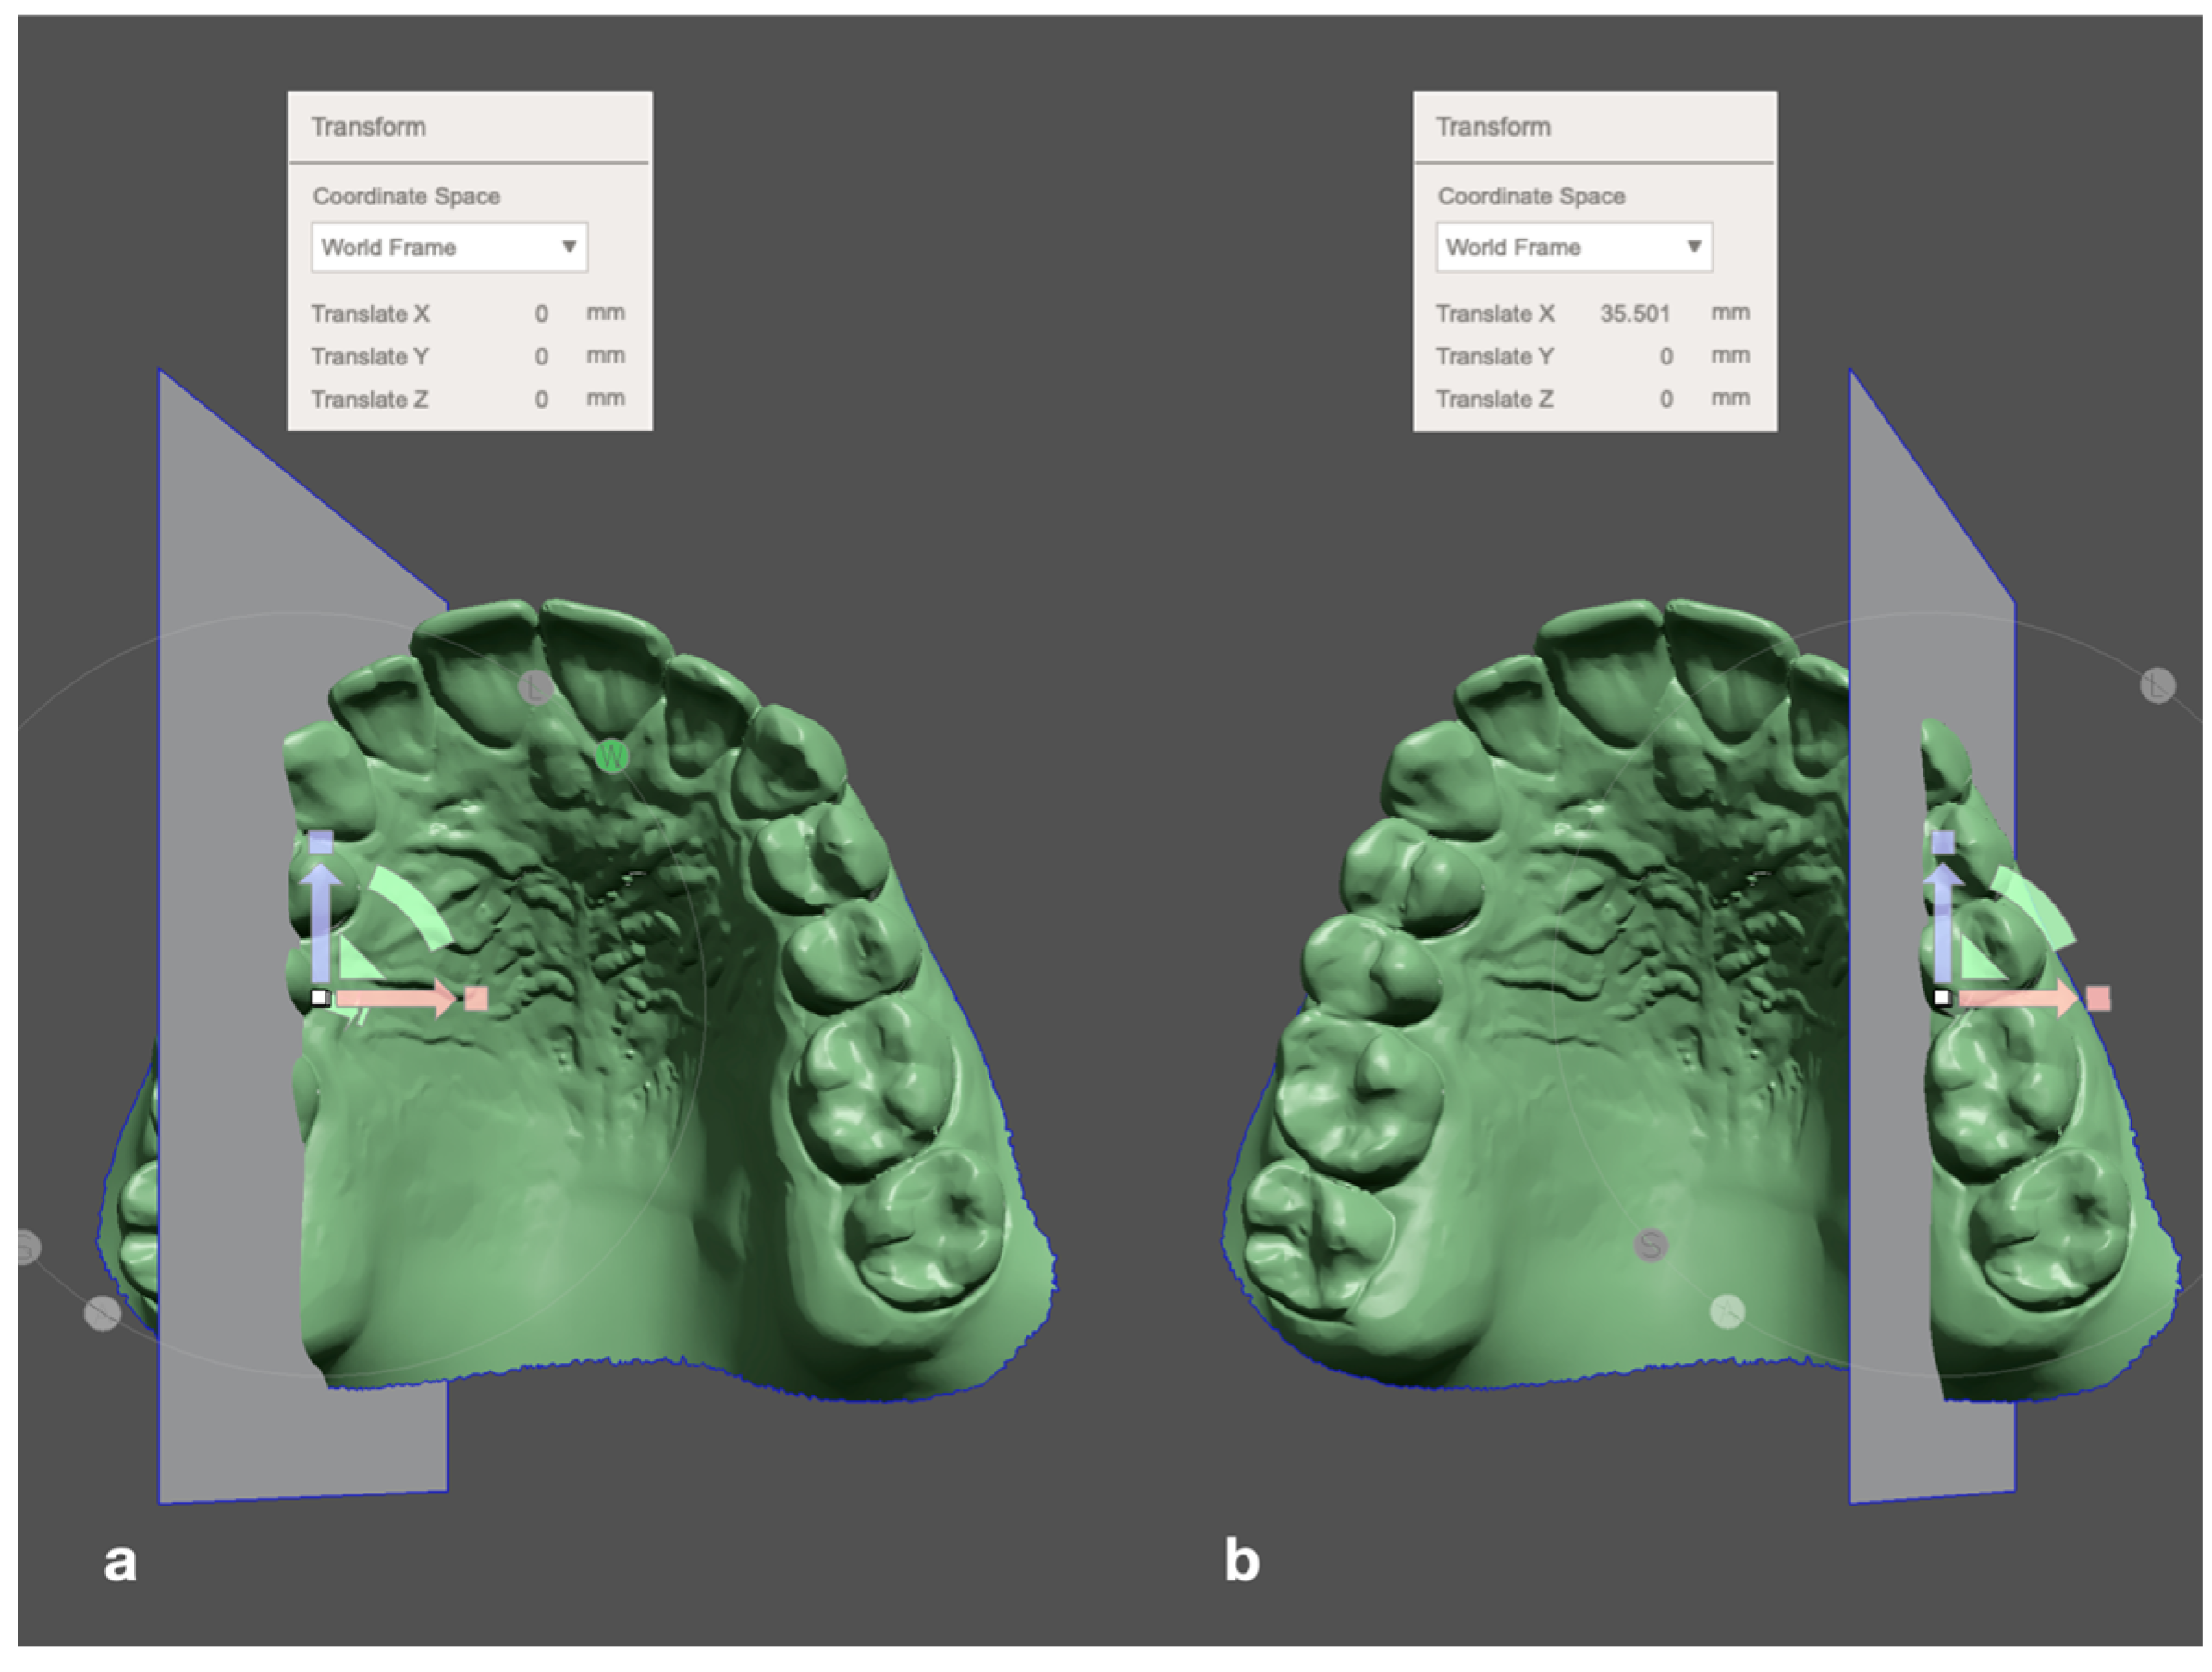

2.1. Measurement Process

- Stamm, T.; Böttcher, D.; Kleinheinz, J. The University Münster Model Surgery System for Orthognathic Surgery-The Digital Update. Head Face Med. 2021, 17, 1–10. [Google Scholar] [CrossRef]